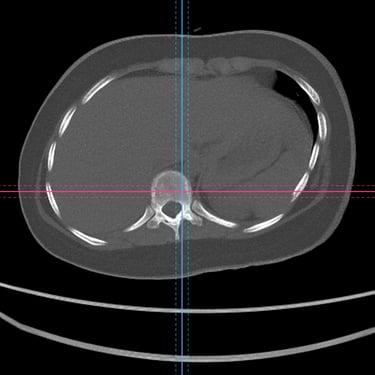

La escoliosis del adolescente idiopática del es una curvatura anormal de la columna vertebral que aparece durante el crecimiento, sin causa identificable. Su diagnóstico se realiza mediante evaluación clínica y estudios por imágenes, principalmente radiografías de columna completa, que permiten medir el ángulo de Cobb y determinar la magnitud de la desviación. En casos complejos o con sospecha de compromiso neurológico, se utiliza resonancia magnética para descartar anomalías medulares. La detección temprana es clave para definir el tratamiento adecuado —observación, uso de corsé o cirugía— y prevenir la progresión de la deformidad.